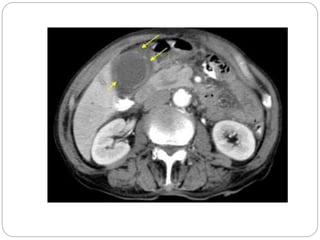

Notice the peripancreatic stranding (bars) as well

as the fluid thickening of the interfascial space

CT Findings typical of pancreatitis include:

1. An enlarged pancreas with infiltration of the

surrounding fat

2. Peripancreatic fluid collections can often be

seen

3. Pseudocysts, (encapsulated fluid

collections containing pancreatic secretions,

are later complications of pancreatitis)